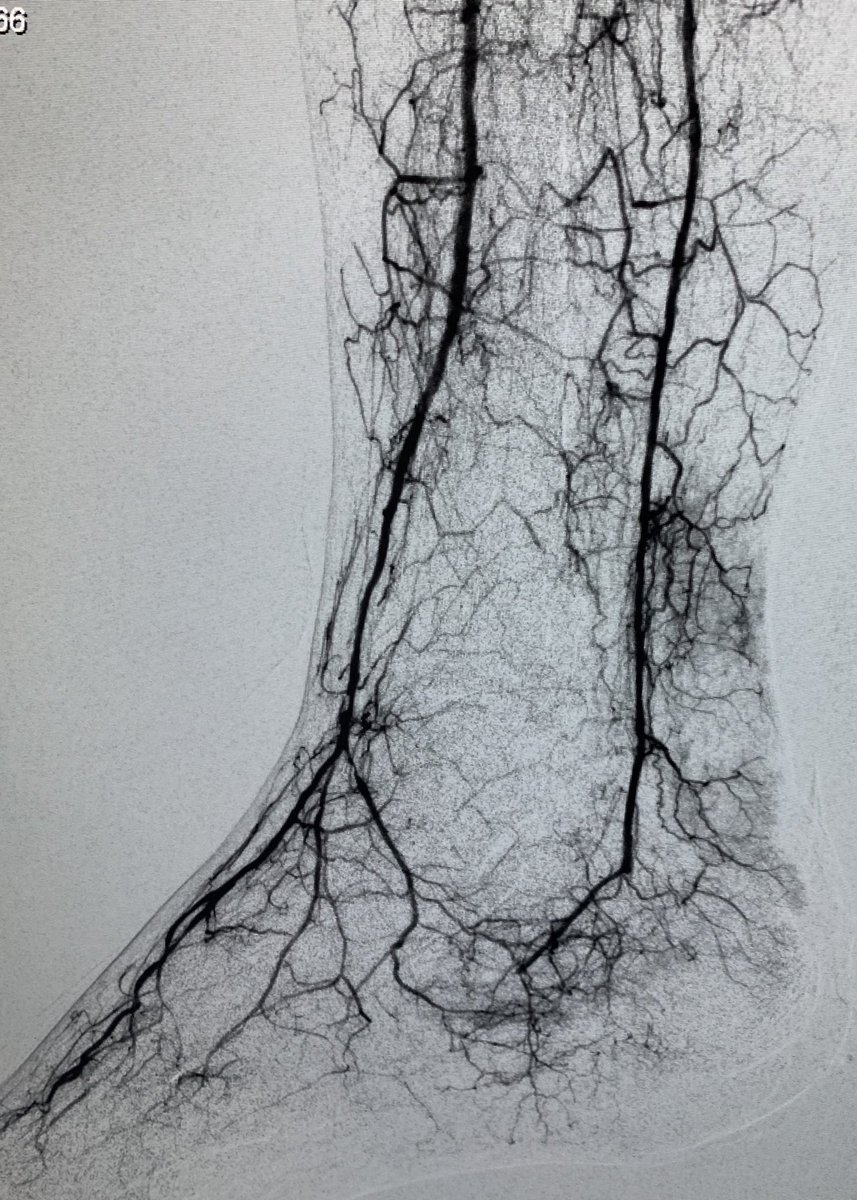

82 yo F with R5 ulcers of 3rd & 4th toes. #IRad can help with infrapopliteal and pedal revascularization to #StopTheChop. #mylegmylife #CLIFighters @SIRspecialists @SIRRFS @CLI_Global @AMPSymposium @pj_rochon

AlexCVIR's tweet image. 82 yo F with R5 ulcers of 3rd & 4th toes. #IRad can help with infrapopliteal and pedal revascularization to #StopTheChop. #mylegmylife #CLIFighters @SIRspecialists @SIRRFS @CLI_Global @AMPSymposium @pj_rochon